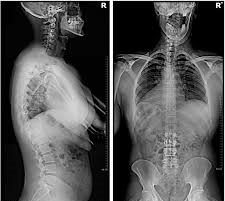

- X-ray analysis – Weight-bearing spinal imaging

A: Yes. Weight-bearing X-rays are a core part of the evaluation process.